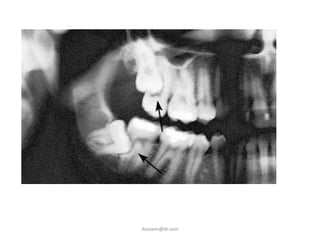

C. Periodontal Disease

• Erupted teeth adjacent to

impacted teeth are

predisposed to periodontal

disease.

• As it decrease amount of bone

on the distal aspect of adjacent

2nd molar, with deep

periodontal pocket on the

distal aspect of the 2nd molar.

D. Root Resorption

• Impacted teeth cause

sufficient pressure on

the root of an adjacent

tooth to cause root

resorption.